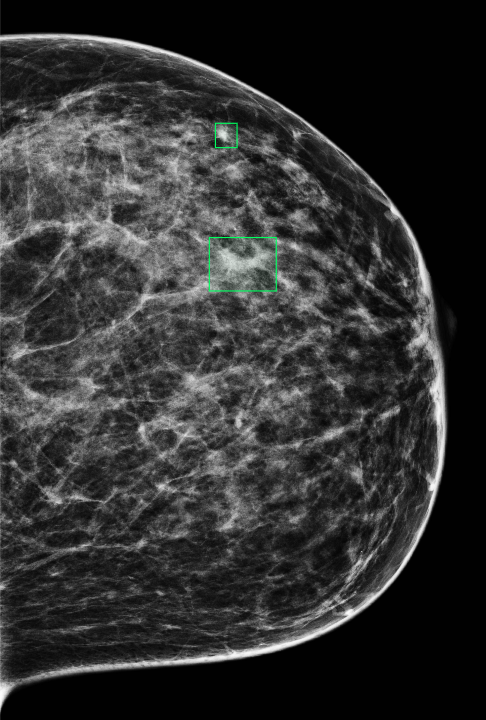

The InBreast dataset was used to evaluate the anomaly segmentation performance. The evaluation scenario is basically zero-shot, as the images tested on are different from those used to train MAMBO on. To allow comparison with existing approaches used in the domain of radiology, only the low-resolution (global context) model was used as described in Sec. 3 and trained on the subset of healthy images taken from the VinDr dataset.

To select the optimal value of the timestep parameter () for the anomaly segmentation task, values in the range were evaluated. The optimal value of , was obtained for all masses in the dataset, corresponding to an IoU of 0.216.

To further probe the capabilities of recognizing lesions of different sizes, Tab. 6 illustrates the performance of MAMBO using the optimal . To produce the data, lesions are grouped in buckets according to size. The size of lesions (in pixels) in the dataset follows an exponential distribution. Lesions are assigned to the buckets using a logarithmic scale, which yields buckets with the same number of images (18) in each, except for the last bucket, which contains 17 images.

| Area (px) | 64 | 128 | 222 | 521 | 951 | 2187 |

|---|---|---|---|---|---|---|

| IoU | 0.019 | 0.069 | 0.125 | 0.280 | 0.423 | 0.393 |

| Area is represented on a log scale, median size is shown for each bucket. | ||||||

As Tab. 6 shows, larger lesions are easier to detect using the model. Exceptions occur when a lesion grows large, nearing breast size, and the model finds it difficult to remove the whole anomaly. Quantitatively, the best result achieved by the proposed approach is as high as , a significant improvement over the reported for AnoDDPM in [44] for brain radiology images.

Figure 10 shows additional results of anomaly segmentation on the InBreast dataset, using the MAMBO low-resolution (global-context) model, for the size of lesion that the approach detects well, as well as one which is challenging for it.